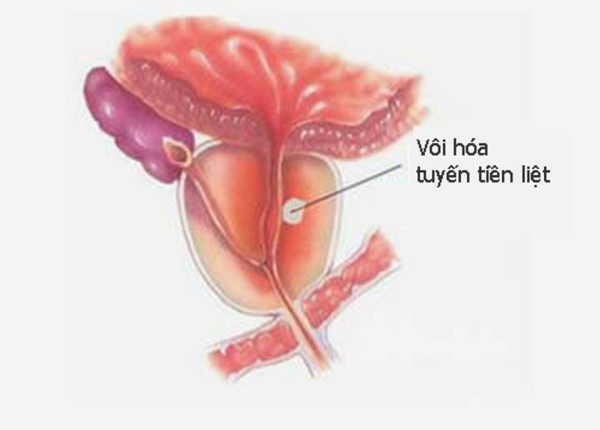

Vôi hóa tiền liệt tuyến là gì?

Giảng viên Cao đẳng Y Dược Hà Nội cho hay, Vôi hóa tiền liệt tuyến là sự tích tụ canxi trong tuyến tiền liệt. Thông thường, tình trạng này không gây ra bất kỳ triệu chứng không thoải mái nào cho bệnh nhân và thường được phát hiện ngẫu nhiên thông qua các phương pháp như siêu âm hoặc chụp X-quang, hiển thị hình ảnh về sự hình thành của các vết vôi.

Vôi hóa tiền liệt tuyến thường xuất hiện sau quá trình viêm nhiễm tuyến tiền liệt, khi sự viêm nhiễm gây ra quá trình xơ hóa trong tuyến. Các điểm vôi hóa có thể hình thành từ những điểm này hoặc do quá trình viêm làm tắc nghẽn ống dẫn tuyến tiền liệt, dẫn đến sự tích tụ chất lỏng và hình thành vôi hóa hoặc sỏi.

Mặc dù nguyên nhân chính của tình trạng vôi hóa tiền liệt tuyến vẫn chưa được hiểu rõ, nhưng quan sát đã chỉ ra rằng nó thường liên quan đến các tình trạng như viêm nhiễm tuyến tiền liệt, phì đại tuyến tiền liệt, ung thư tuyến tiền liệt, sau quá trình phẫu thuật phì đại, hoặc sau điều trị ung thư tuyến tiền liệt.